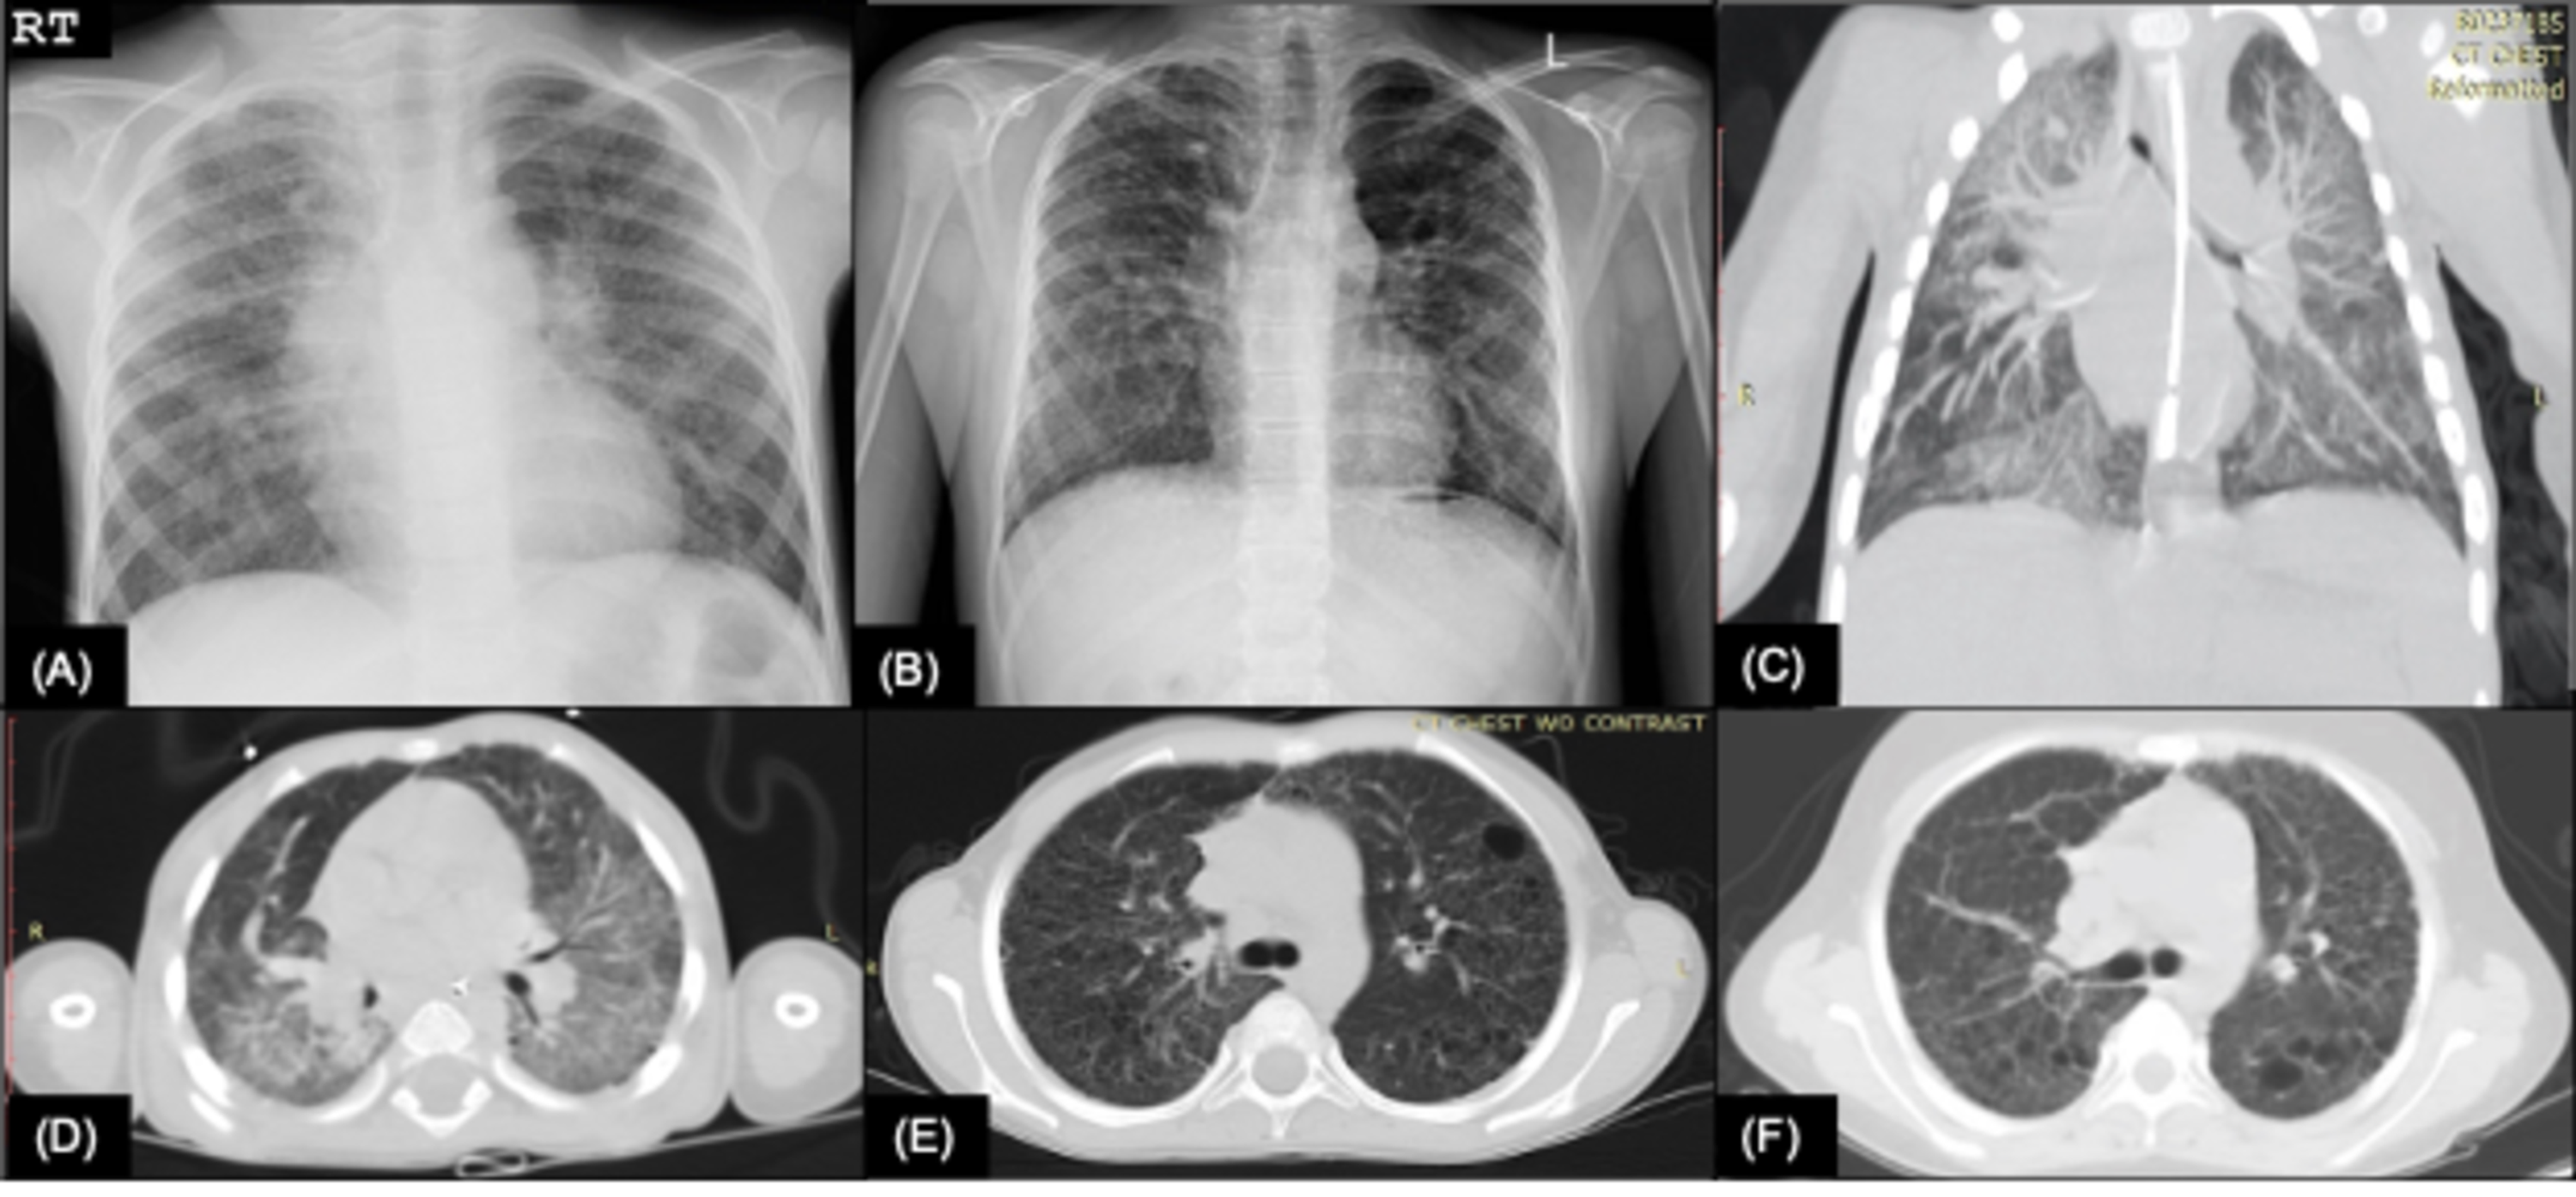

From www.cureus.com

Cureus Surfactant Protein C Deficiency in a Puerto Rican Adolescent Protein C Deficiency Rare Web inheritance of protein c deficiency is rare but important to recognise as it is one of the thrombophilias with the greatest risk of thrombosis. Web however, establishing a diagnosis of hereditary protein c deficiency can be difficult, as many clinical states. Web protein c deficiency is a rare disorder, characterized by a reduction in the activity of protein c,. Protein C Deficiency Rare.